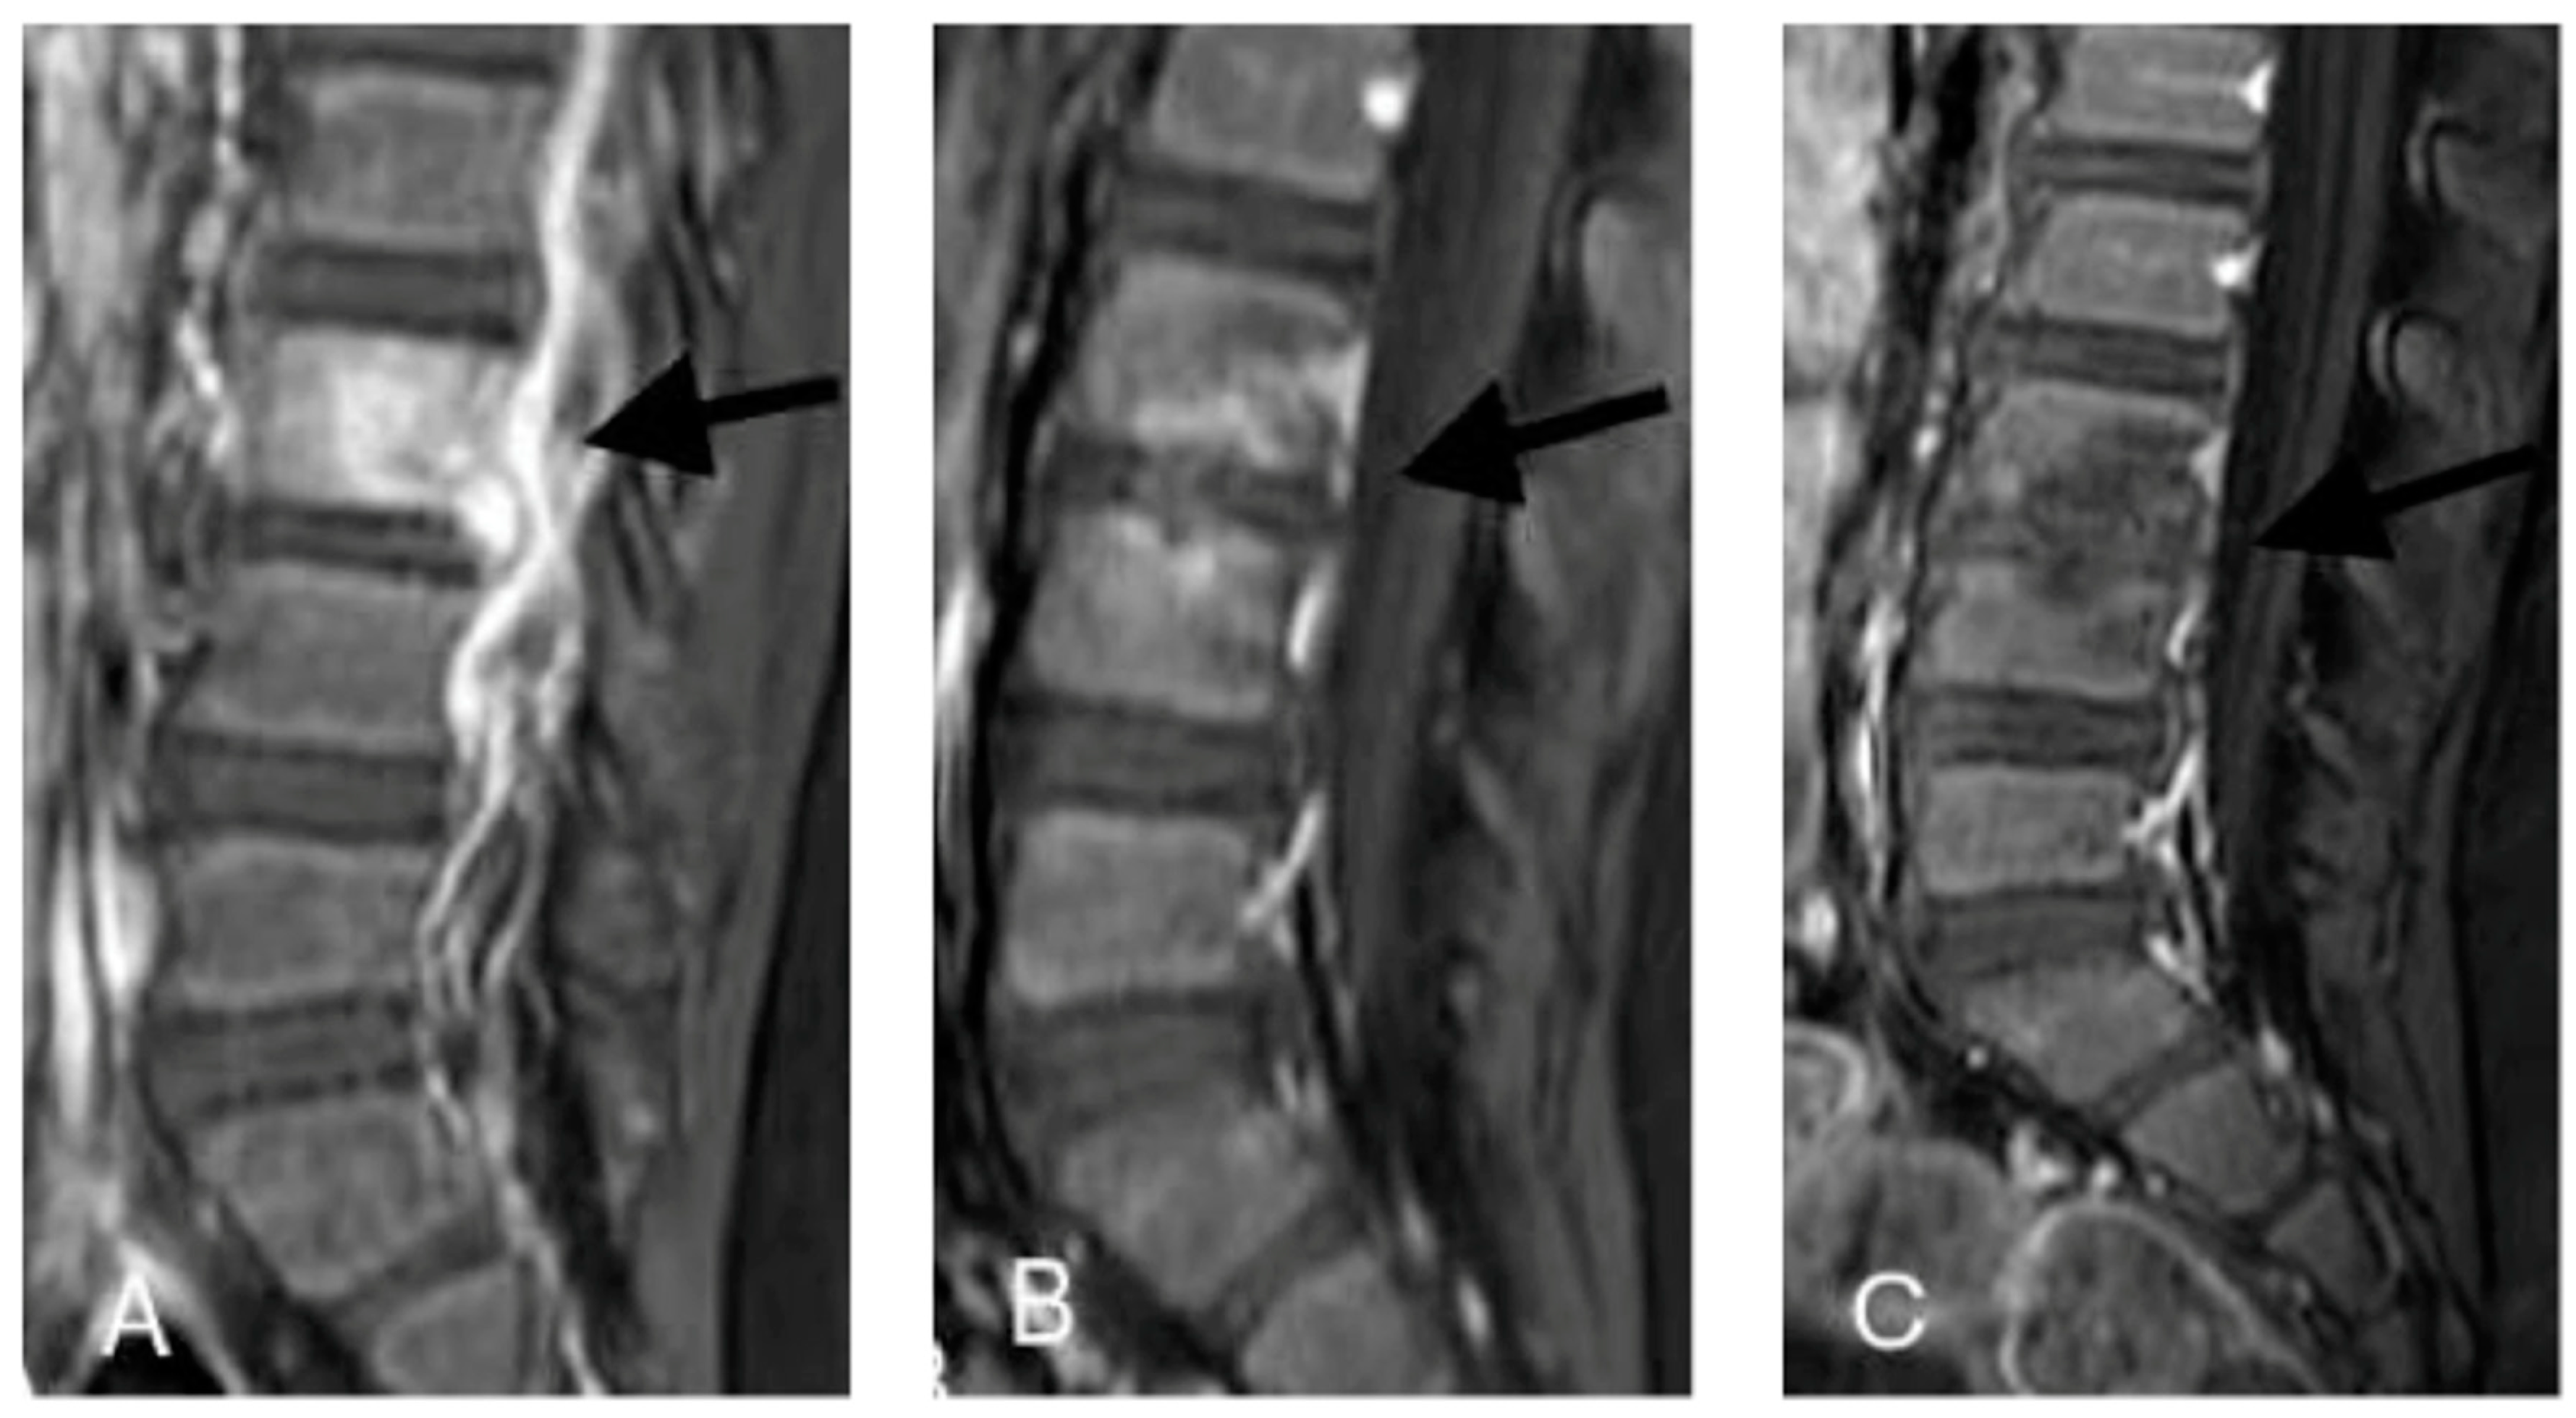

2.1. Case 1

2.2. Case 2